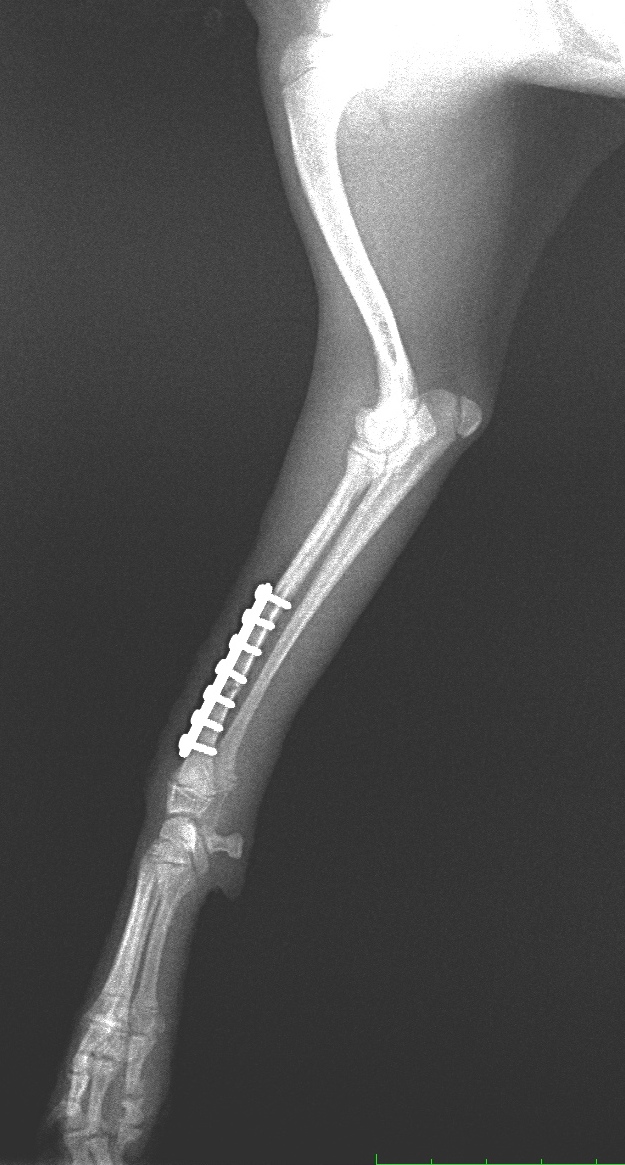

1.プレート固定(コンベンショナル、ロッキング)

上腕骨粉砕骨折 脛骨近位骨折

脛骨遠位骨折 大腿骨骨折